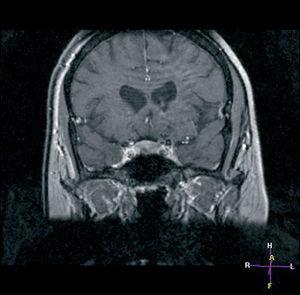

Por último, se realizó una una resonancia magnética (RM) hipofisaria que evidenció un microadenoma hipofisario de 0,6 mm en hemihipófisis derecha e inferior (fig. 2).

Figura 2.RM hipofisaria. Corte coronal donde puede apreciarse el microadenoma hipofisario causante de la enfermedad de Cushing.